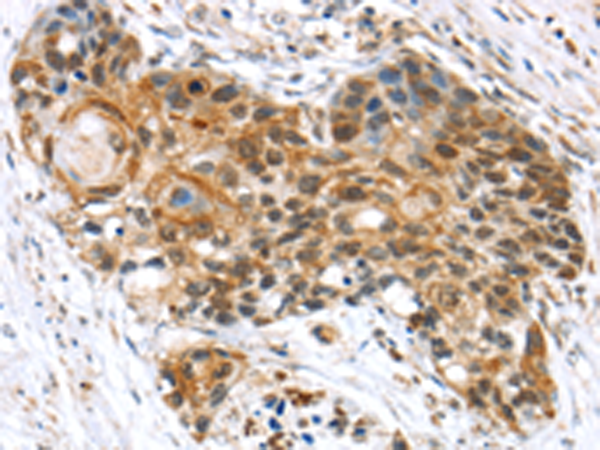

分类: 科研抗体货号: P05398别名: SIII; TCEB3; TCEB3A; SIII p110应用: IHC反应种属: Human